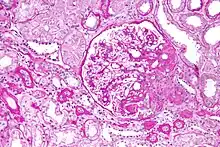

Light micrograph of focal segmental glomerulosclerosis, hilar variant. Kidney biopsy. PAS stain.

On histology, FSGS manifests as scarring (sclerosis) to segments of glomeruli; moreover, only a portion of glomeruli are affected.[7][20][21] The focal and segmental nature of disease seen on histology help to distinguish FSGS from other types of glomerular sclerosis.[21]

Diagnosis of FSGS is made by renal biopsy that includes at least fifteen serial cuts with at least eight glomeruli.[31][32] Histologic features include sclerosis (scarring) of a portion (average: 15%) of the glomerular space, with only a portion of glomeruli manifesting any sclerosis.[32]